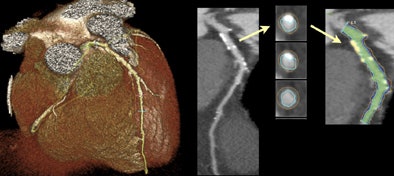

| Calcium can be readily identified on contrast-enhanced coronary CTA. After selecting an arterial segment with a software tool and making any necessary adjustments, the volume of high-intensity calcium can be measured. The calcium volume is converted to the Agatson score with a standard linear conversion factor. All images courtesy of James Otton. |

They identified calcifications by windowing and examining each axial slice in minimal slice thickness, as well as thick maximum intensity projection (MIP) and curved multiplanar reconstruction (MPR) views, Otton told AuntMinnie.com.

If an area of possible arterial calcification was seen, the calcium-containing arterial segment was selected in curved multiplanar view utilizing the SurePlaque plaque quantification software (VitreaFX v3.1, Toshiba).

The quality of automated arterial edge detection was also visually examined in arterial cross section reconstructed at 1-mm intervals along the arterial segment and was manually adjusted, as necessary, to include calcium deposits within the vessel wall and exclude luminal contrast.

The SurePlaque tool was adjusted to quantify the volume of high-intensity voxels exceeding 320 HU within the selected areas. The final Agatston calcium score estimate was obtained by multiplying the measured calcium volume by the empiric conversion factor.